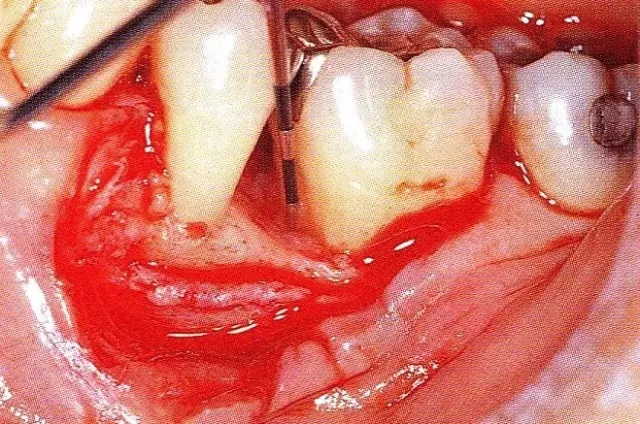

▲圖7-4  術(shù)后1年2個月再翻開看的情況。與圖7-1的骨缺損狀態(tài)相比可知形成了臨床性骨再生。

▲圖7-5  此狀態(tài)下,左下5的遠中存在牙槽骨不平整,因此進行了骨修整。同時,將骨膜留存,進行了齦瓣根尖側(cè)移動術(shù),去除了牙周袋。